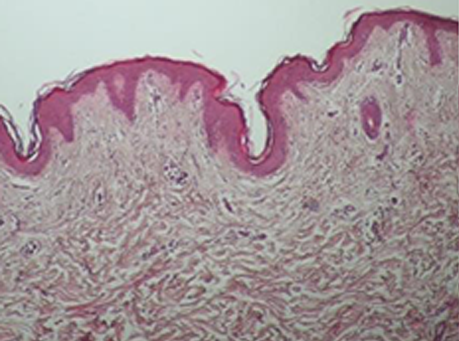

콜라겐 활성의 변화

ONDA 시술 후 진피의 콜라겐이 활성화 되었음을 알 수 있고, ONDA의 에너지가 열로 변환되면서

늘어져 있던 콜라겐을 수축시키고 리모델링을 통해 스킨 타이트닝과 리프팅 효과가 동시에 있음을 확인할 수 있습니다.